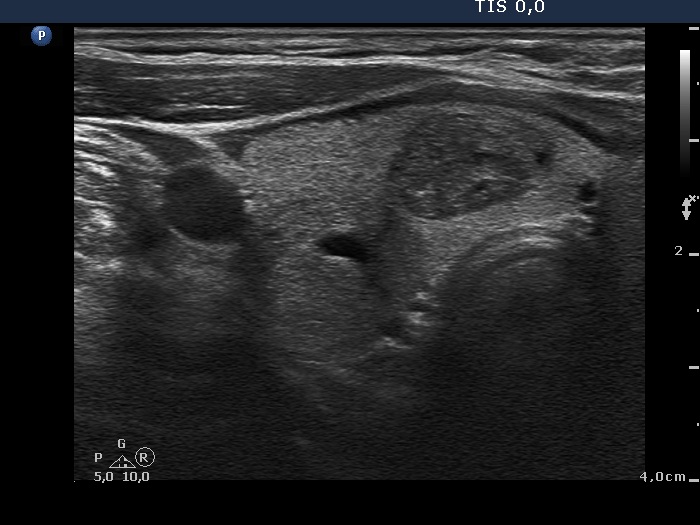

100 consecutive patients with thyroid nodule - Case 35. (ultrasonographic picture 2)

Lower part of the right lobe, horizontal scan. Two more nodules are dmonstrated.